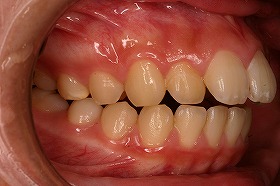

東京世田谷矯正歯科センターで、治療を進めると

出っ歯も後ろに下がり、噛み合わせもキレイになりました。

さらに上の歯が下の歯とあたるようになり、

とても食事がしやすくなったと喜んでいました。